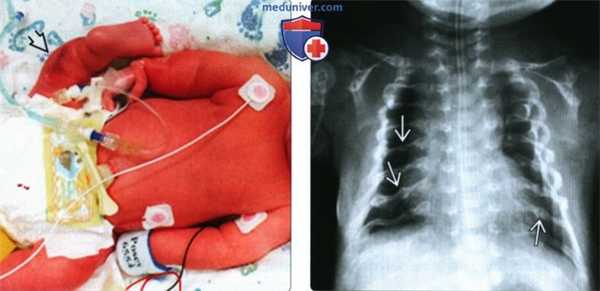

(Слева) Клиническая фотография новорожденного с НО. Клиническая форма -между перинатально-летальным (II тип) и прогрессирующим деформирующим (III тип) типами. Грудная клетка уменьшена, конечности укорочены. Множественные переломы конечностей, особенно ног, создают видимость их искривления.

(Справа) Тот же случай. Рентгенография грудной клетки. Грудная клетка незначительно уменьшена. Множественные переломы ребер. Проявления менее тяжелые, чем при перинатально-летальном НО.